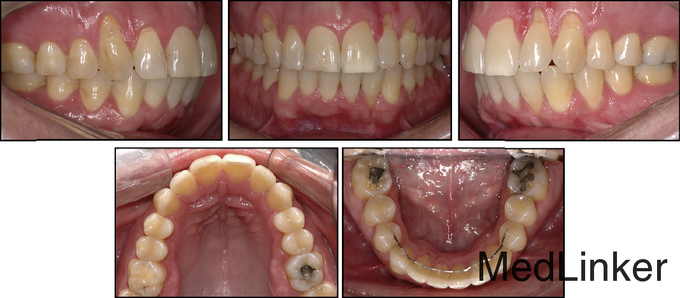

36岁,男性,主诉下颌左侧侧切牙唇侧牙龈退缩明显,伴有疼、刺激痛症状。 骨性牙性II类已经在几年前于外院矫治完成,,上颌佩戴可摘保持器,下颌3-3舌侧丝粘接保持

舌侧丝保持器在右侧侧切牙与尖牙间被破坏,右侧中切牙与侧切牙舌向移动,而左侧尖牙唇向移动。下颌运动过程中,左下2承受了切导的全部负荷。左下2活力测试显示无活力。CT矢状向显示32牙完全位于骨皮质外,32牙根尖1/3横断面显示牙根周围无骨质包绕

治疗计划:左下2行根管治疗,同时通过正畸重新定位。 治疗:32牙行根管治疗,下颌21*25不锈钢弓丝无力被动入槽稳定下牙弓(避开32牙,不结扎32牙),同时弯制带有根舌向转矩的19*25的TMA弓丝,前段只结扎到32牙,双侧后段插入第一恒磨牙颊管中,每个月加大转矩,持续5个月,在第五个月的时候,可见到32牙根尖已有软组织覆盖。此时上颌上矫治器,排齐整平。总疗程14个月。术后牙周探诊32牙唇侧牙周袋只有1mm。刺激痛症状消失。下颌4-4由16*22不锈钢弯制的舌侧丝保持。1年后复诊,效果仍然稳定。